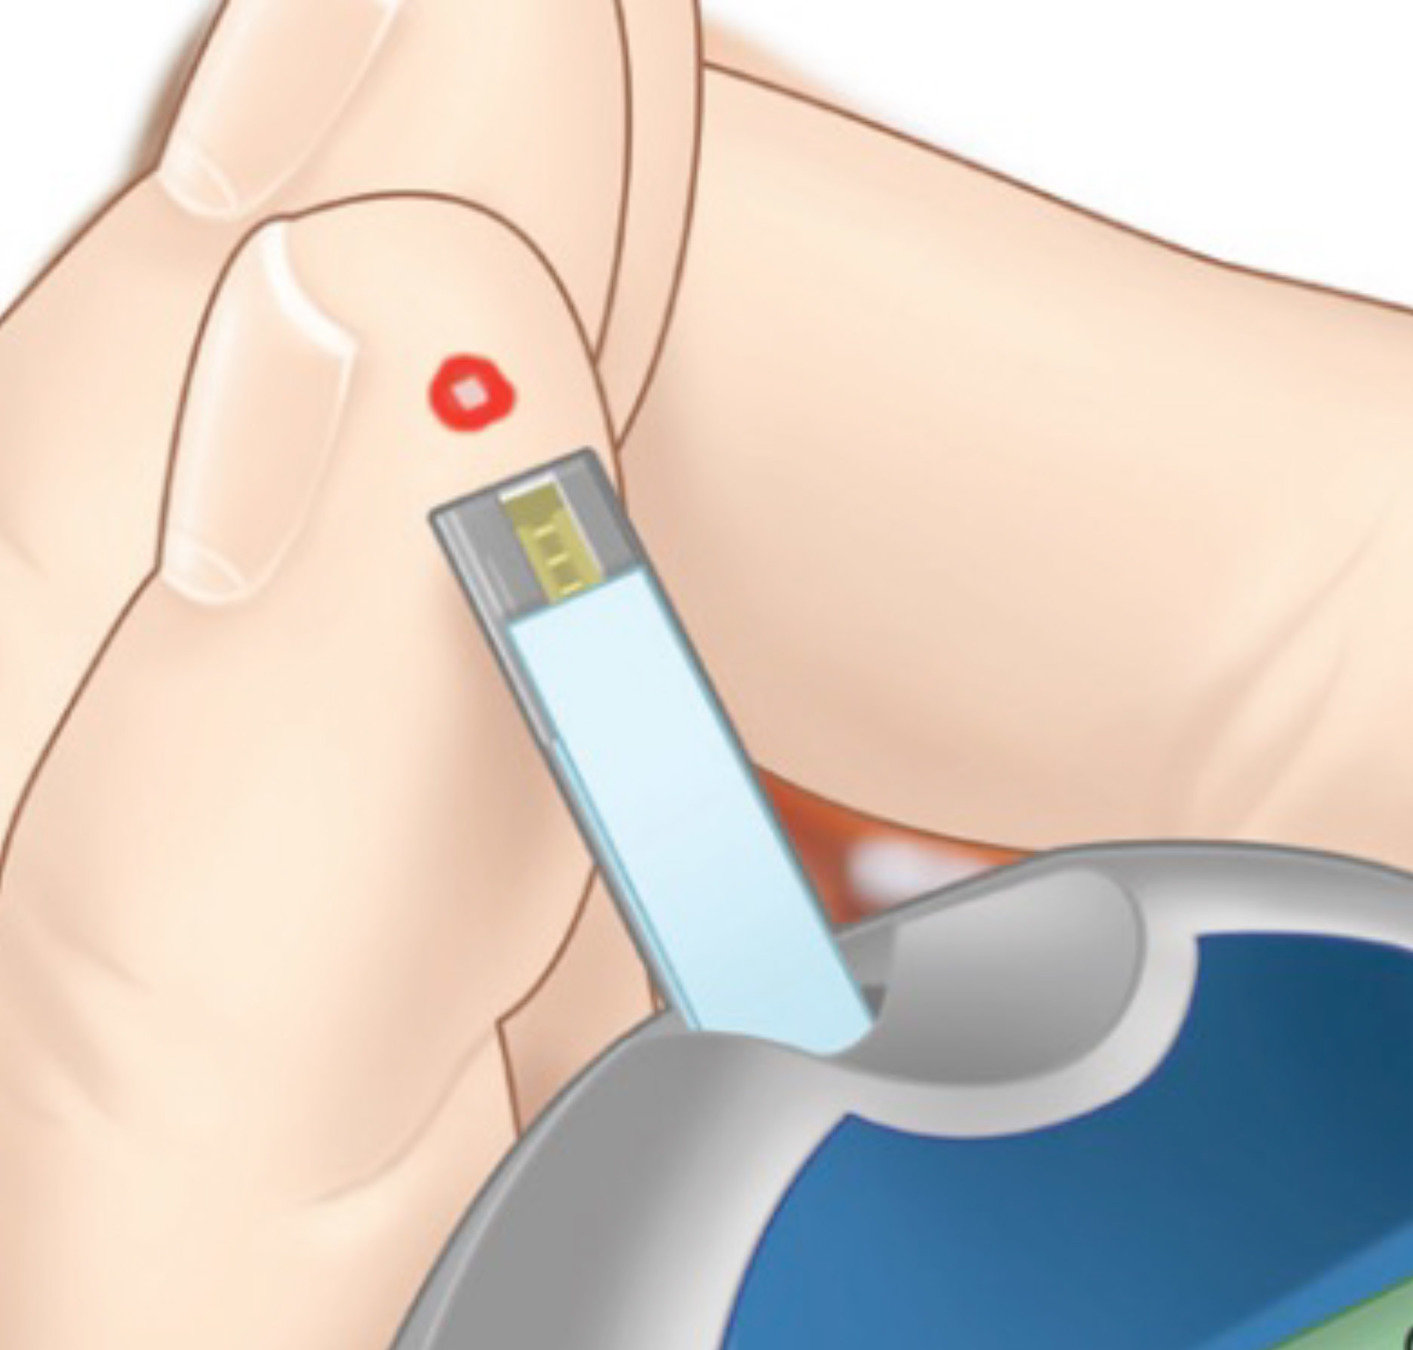

Para introducir una calibración, haga una comprobación de glucosa en sangre mediante punción capilar…

… y toque en el botón Calibrar.

- Lávese siempre bien las manos y séqueselas por completo.

- Introduzca siempre un valor de glucosa en sangre real e introduzca la calibración antes de que transcurran 10 minutos desde la obtención de la glucosa capilar.

- Y, por último, mantenga el transmisor inteligente en su sitio encima del sensor Eversense® E3 durante al menos 5 minutos antes y 15 minutos después de cada calibración.

- Y, al calibrar, utilice siempre el medidor de glucosa en sangre e introduzca un valor de glucosa en sangre real obtenido mediante punción capilar. Introduzca el valor de calibración en el plazo de 10 minutos y recuerde que el transmisor inteligente debe permanecer sobre el brazo durante al menos 5 minutos antes y 15 minutos después de que introduzca el valor de calibración.